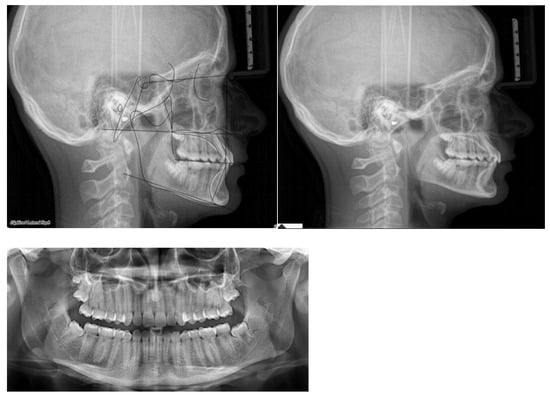

Post-treatment lateral teleradiograph showed a significant improvement in the sagittal bone relationship (Table 1), along with good vertical control, and a correct inclination of the upper and mandibular incisors. (Figure 4). A good proportion between the upper and mandibular arch width and shape was achieved along with a flat curve of Spee. Functional and aesthetic outcomes were stable at one-year follow-up and four-year follow-up (Figure 4, Figure 5 and Figure 6).

Figure 6.

Cephalometric changes.